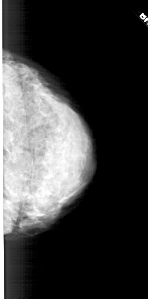

A_1775_1.LEFT_CC

LEFT_CC LINES 5191 PIXELS_PER_LINE 1921 BITS_PER_PIXEL 12 RESOLUTION 43.5 OVERLAY